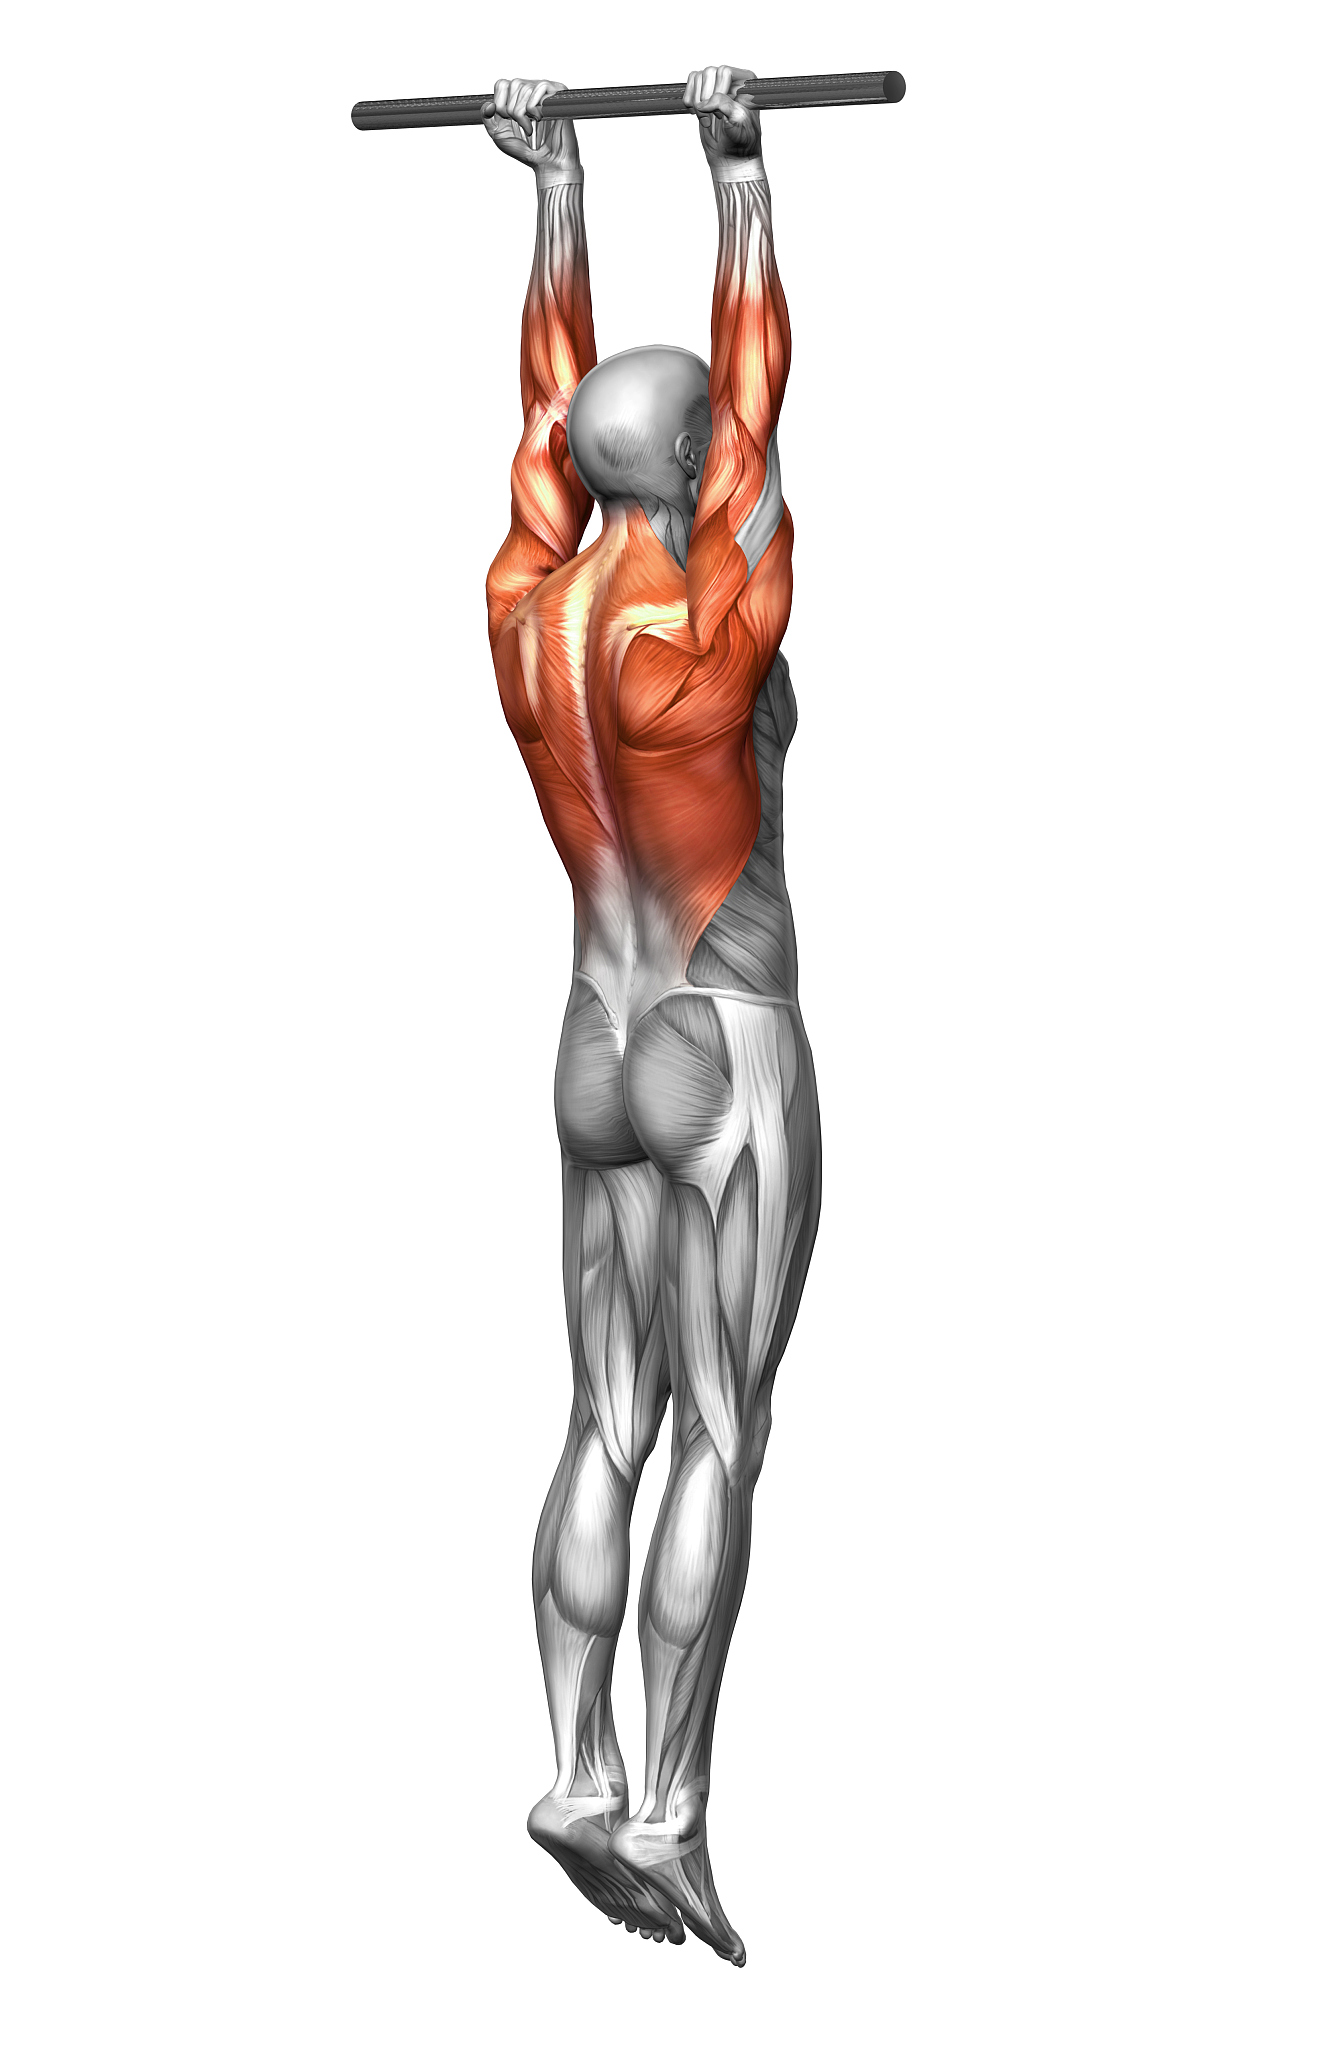

肩部肌腱炎通常影响肩关节周围的几条肌腱,其中最常见的受累肌腱是冈上肌和肱二头肌长头。冈上肌是肩袖肌群的一部分,负责肩关节的外旋和外展;肱二头肌长头则有助于肩关节的屈曲和外旋。

当这些肌腱受到过度使用、损伤或其他因素的影响时,就会发生炎症和疼痛,导致肩部肌腱炎。